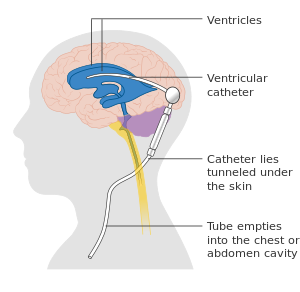

- في حالات وجود انسداد في طريق الدورة الطبيعية للسائل، فإن إيجاد مخرج لهذا السائل مهم جداً، وحيث أنه لا يمكن التدخل لعلاج الانسداد الموجود، فإن إيجاد مخرج آخر لتقليل الضغط داخل الدماغ مهم، حيث يقوم جراح الأعصاب بعمل توصيل بين بطينات المخ وتجويف القلب أو تجويف البطن لتصريف السائل فيما يعرف بالتَحْويلة الدماغِية (Cerebral shunt) [15].

يقوم الجراح بإدخال أنبوبة في البطين الجانبي، وتخرج من عظمة الجمجمة، وهناك يمكن وضع صمام للتحكم في كمية السائل المتحرك معتمداً على توازن الضغط داخل البطين، ومن هذا الصمام وتحت الجلد تكون هناك أنبوبة متصلة عبر الرقبة والصدر لتنتهي في البطن، حيث يصل السائل الدماغي الشوكي الزائد ويمتص من خلال الغشاء البريتوني، عادة تكون الأنبوبة الموصلة طويلة لكي لا يُضطر إلى تغيير الأنبوبة مع نمو الطفل.

- وهناك علاج آخر لأنواع معينة من استسقاء المخ الناجم عن انسداد الثقوب بين البطينات، وهو يعتمد على ثقب قاعدة البطين الثالث لتصريف السائل، وتتم العملية باستخدام منظار داخلي. يطلق على هذا العلاج اسم "الافتغار بالمنظار الداخلي" لقاعدة البطين الثالث (Endoscopic neostomy) [10].

استسقاء الرأس الداخلي يمكن أن يتم علاجه بطريقة ناجحة من خلال عمل توصيلة بين بطينات الدماغ وتجويف البطن لإزالة الضغط العالي داخل القحف الدماغي. هناك خطر من الإصابة بالعدوى نتيجة لإدخال هذه التوصيلة إلى الدماغ، ومع ذلك، هذه التوصيلات يجب أن يتم استبدالها مع نمو الشخص. إذا حدث نزيف في المنطقة تحت العنكبوتية يمكن أن ينتج عنه انسداد في عودة السائل النخاعي إلى الدورة الدموية.